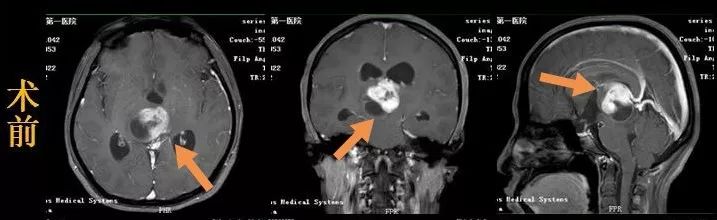

5月中旬,刘女士家人赶紧陪她到南京市第一医院,我院神经外科主任樊友武接诊后,立马对刘女士进行了头颅核磁共振检查,检查结果显示刘女士异常信号的占位病灶。结合磁共振平扫,专家组诊断为松果体区肿瘤合并梗阻性脑积水,高度怀疑是脑胶质瘤。

樊主任介绍,松果体区位置极深,手术难度极大,肿瘤前方是中脑背侧,紧贴脑干,上方是大脑内静脉,后方紧贴大脑大静脉,下方是四叠体池。尤其是深静脉系统负责引*脑流**干及大脑深部脑组织血供,如手术出现静脉性损伤,可能引起深部脑组织肿胀出血,出现昏迷甚至生命危险。

专家们经过反复的术前讨论和精心准备,由樊友武主任主刀为刘女士实施手术,手术采用改良POPPEN入路,牵开左侧枕叶,切开小脑幕显露肿瘤,然后小心避开大脑大静脉及大脑内静脉,在脑干背侧仔细辨认肿瘤界限,分块切除。持续近两个小时在显微镜下操作的手术,终于将肿瘤完全切除。

病理切片结果确诊为毛细胞型星型细胞瘤,属于低级别胶质瘤。随后专家充分利用手术切口,经侧脑室枕角穿刺,将分流管绕过中脑导水管的梗阻部位,另一端向下放入枕大池,等于重建了脑脊液的循环通路,同期解决了梗阻性脑积水的问题。